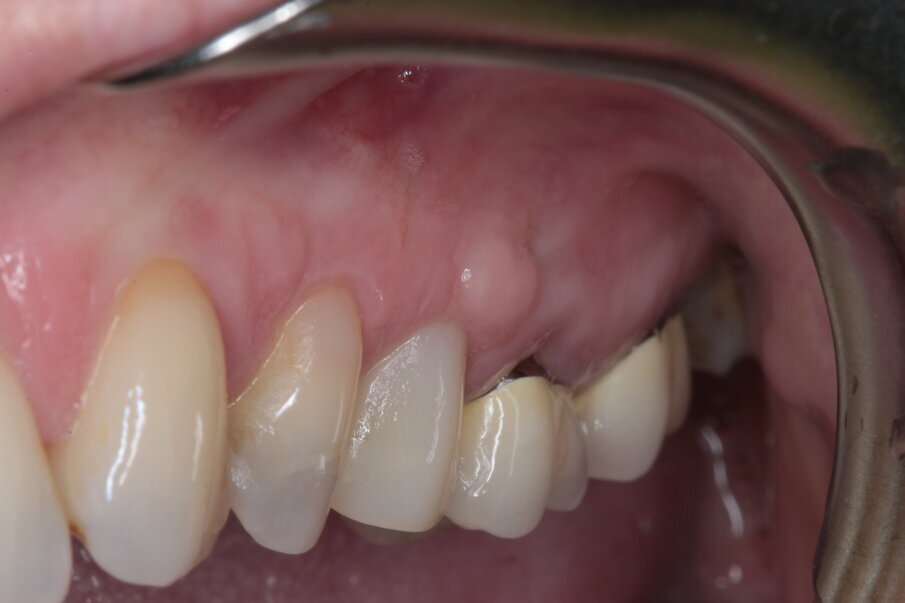

La paziente si presenta in visita lamentando mobilità e l’insorgenza di un dolore alla masticazione a carico dell’elemento 25. Clinicamente l’elemento presenta una corona in ceramica integrale realizzata anni prima (non ricorda quanti) presso altra sede, mobilità di II grado e sondaggio di 9 mm sul versante palatale.

Si presenta inoltre dolente alla percussione. Si riscontra anche l’assenza di risposta al test di vitalità dell’elemento 24, sul quale la paziente riferisce sia stata effettuata una medicazione endodontica da un collega come tentativo di risolvere la sintomatologia dolorosa a carico dell’elemento 25 (Figg. 1-3).